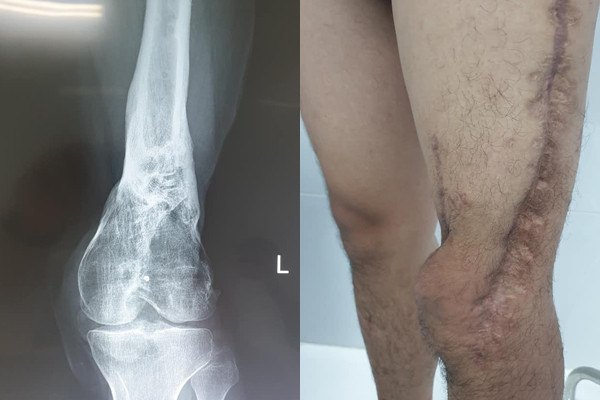

| Hình ảnh chân trái của bệnh nhân trên phim X-quang cho thấy gần như bị hoại tử hết phía trong (trái) và đôi chân của bệnh nhân sau 7 lần phẫu thuật. |

Cách đây 5 năm, H. bị tai nạn xe máy, chân trái gãy hở rất phức tạp, mất xương trên lồi cầu, liên lồi cầu xương đùi và nhiễm trùng rất nặng.

May mắn, đến lần mổ thứ 4, chân H. đã hết nhiễm trùng, hết xương chết và cơ thối. Tuy nhiên bệnh nhân bị khuyết xương đùi và cứng khớp gối, mất gân cơ quanh đùi, đi lại hết sức khó khăn.

Lần thứ 6 rồi lần thứ 7, chàng trai trẻ lại lên bàn mổ. May mắn đôi chân em đã hồi phục, H. đi làm trở lại và mới đây thông báo với BS Tùng tin vui sắp lấy vợ.